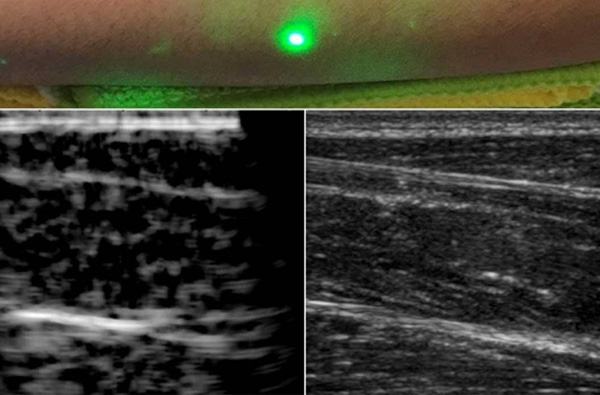

全球首張人類激光超聲波圖像問(wèn)世

東莞盈創(chuàng)激光科技有限公司,詳細(xì)概述,與其他成像方法相比,超聲成像具有非電離、成本相對(duì)較低、便于攜帶等優(yōu)點(diǎn)。 如果需要進(jìn)行超聲波檢查,但患者不能忍受探針接觸皮膚,例如嬰兒或燒傷患者,則需要更好的技術(shù)。 現(xiàn)在,麻省...